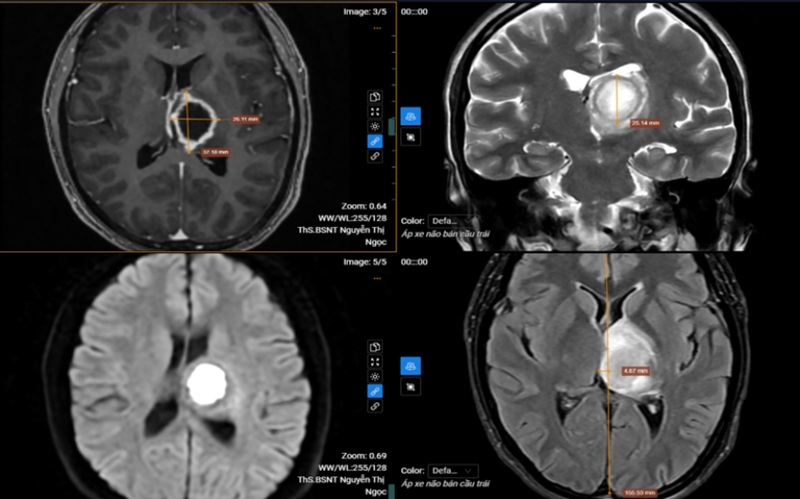

Chụp cộng hưởng từ (MRI) sọ não, bác sĩ phát hiện tổn thương khu trú tại vùng đồi thị – vành tia bên trái. Tổn thương dạng dịch, kích thước khoảng 26x37x25 mm, ranh giới rõ, bờ không đều, phần trung tâm hạn chế khuếch tán, sau tiêm ngấm thuốc viền, vùng xung quanh xuất hiện phù não, gây hiệu ứng khối làm đẩy lệch đường giữa sang phải khoảng 5mm. Chụp cộng hưởng từ phổ cho thấy, giảm Choline và NAA, tăng Lipid và Lactate.

Kết quả MRI phát hiện tổn thương khu trú tại vùng đồi thị – vành tia bên trái